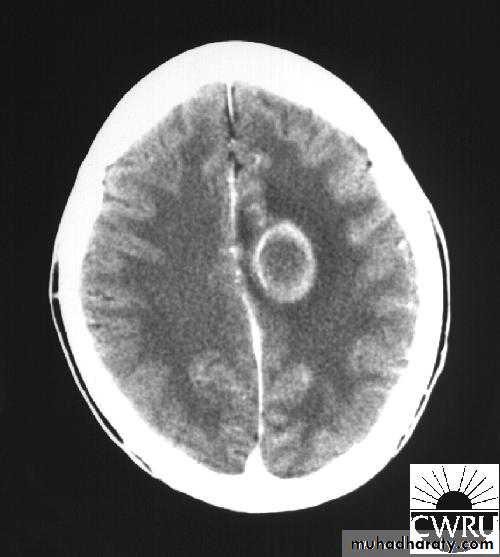

• B. Radiological Investigations:

• CT or MRI is the investigation of choice.

• CT Brain is performed with and without contrast.

• MRI is done with gadolinium enhancement.

• They will show a single (or multiple) space occupying lesion that is well delineated with an enhancing wall, with variable surrounding oedema.

Brain Abscess CT with contrast

د.عبدالرحمن